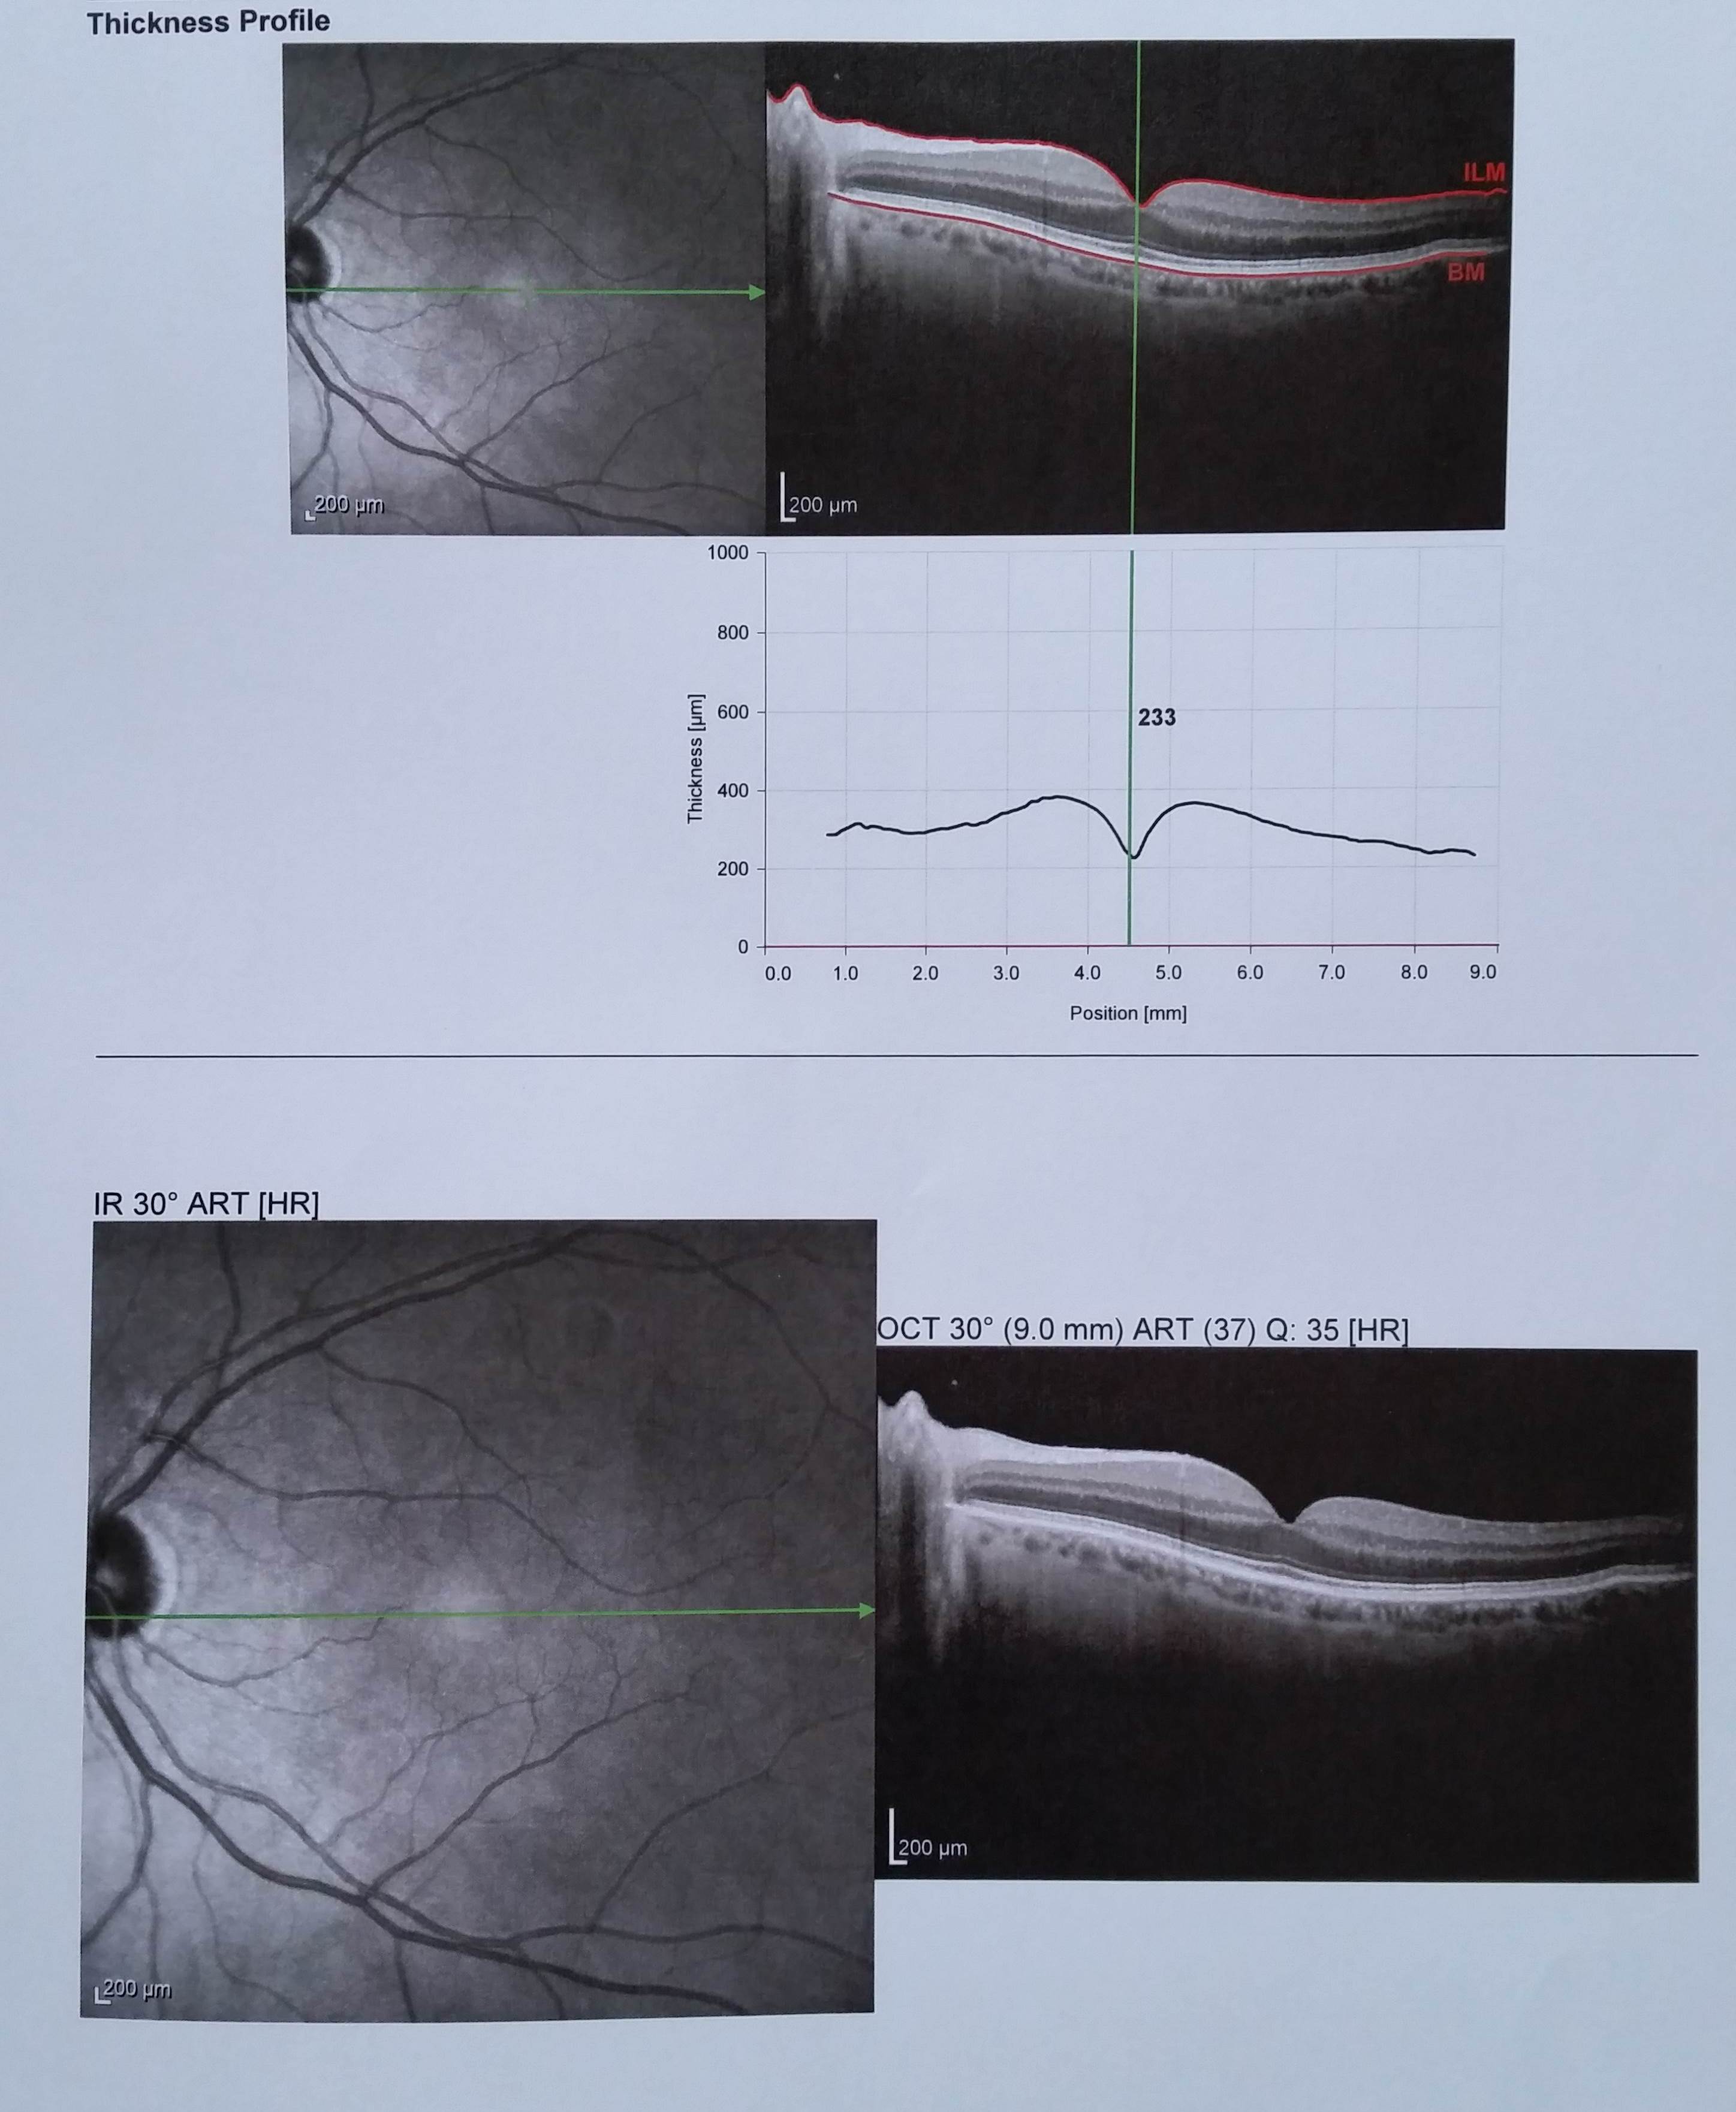

8 Pucker maculare indicazione a controlli clinico-strumentali

Paziente di 69 anni riferito calo visivo nell'occhio destro senza metamorfopsie (immagini deformate), l'obiettività oculistica è la seguente:

vod:8/10 sf-3

vos:10/10 sf-3

too:15 mmhg

boo:diottri anteriori nei limiti di norma per l'età

fod:pucker maculare

fos:polo posteriore nei limiti di norma

Effettuato OCT (vedi allegato) viene confermato il pucker maculare nell'occhio destro In considerazione del visus elevato e dell'assenza di metamorfopsie si decide di tenere controllato il paziente con visite oculistiche e OCT.

Se verrà notato un peggioramento del quadro clinico con riduzione della vista comparsa di metamorfopsie e progressione del pucker visibile all'OCT si consiglierà l'intervento in caso contrario se la situazione resterà stabile si continuerà a tenerla controllata.